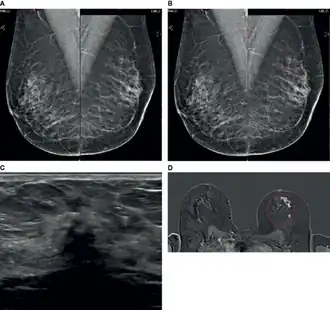

Le diagnostic de cancer lobulaire par examen physique peut être difficile car les patientes présentent souvent des signes cliniques limités et n'ont pas toujours de masse mammaire palpable ; les signes peuvent être souvent vagues, comme un épaississement de la peau ou une sensation de capitonnage de la peau. La mammographie et l'échographie du sein ont une faible sensibilité pour détecter le cancer lobulaire par rapport aux autres tumeurs invasives du sein. Cette difficulté peut être largement attribuée au modèle de croissance infiltrante diffuse de ce type de cancer.

Mammographie

La mammographie est considérée comme la méthode d'imagerie de référence » pour la détection précoce du cancer du sein , avec une sensibilité allant généralement de 63 % à 98 %. Ceci est réalisé en produisant des images haute résolution, mettant en évidence les différences de contraste entre les tissus mammaires sains et malins [26]. La détection de cancer lobulaire par mammographie est notoirement difficile en raison du modèle de croissance tumorale infiltrant qui ne détruit pas les structures anatomiques sous-jacentes et ne provoque pas de réaction stromale. En raison de ces caractéristiques tumorales , la sensibilité de détection du cancer lobulaire par mammographie est beaucoup plus faible, comprise entre 57 % et 81 %. Les faux positifs ne sont pas non plus rares, avec des taux rapportés allant de 8 % à 24 % [27]. Le taux de faux négatifs dans le diagnostic de cancer lobulaire est beaucoup plus élevé que celui des autres cancers du sein invasifs [28]. Plus de la moitié des mammographies jugées ne montrant aucun signe de malignité se sont ensuite révélées évocatrices d’une tumeur.

La relation inverse entre la densité du tissu mammaire et la sensibilité mammographique est bien établie. Dans le cas de tissu mammaire extrêmement dense, la détection mammographique peut être aussi faible que 30 % [26]. Dans une étude [29] la sensibilité mammographique s'est avérée être d'environ 34 % dans les cas de cancer lobulaire et, après ajustement pour les patientes présentant un tissu mammaire dense, la sensibilité a diminué à seulement 11 %. En plus de son schéma de croissance histologique distinct, une faible opacité peut également expliquer les difficultés liées à l'identification clinique de cancer lobulaire par mammographie [30]. Une autre étude [31] rapporte que jusqu'à 50 % des cancers lobulaires présentent un manque d'opacité inférieur ou égal au tissu mammaire normal lors de l'imagerie. Ce manque de contraste met en évidence la difficulté de délimiter les tissus mammaires malins du cancer lobulaire et normaux à l'aide de la mammographie conventionnelle [26]. Les carcinomes invasifs sont souvent associés à des masses spiculées de haute densité, dues à la perturbation de l'architecture normale du tissu mammaire. Ce type de masse peut être facilement détecté par mammographie. Les rapports suggèrent que le cancer lobulaire se manifeste par des lésions mal spiculées et mal définies, avec une masse bien définie observée dans moins de 1 % des cas [26]. De plus, jusqu'à 35 % des cancers lobulaires ne seraient visibles que sur la vue craniocaudale [27]. Cela peut également contribuer à rendre les estimations de la taille et de l’étendue de la tumeur moins fiables [32]. Les microcalcifications sont souvent considérées comme des indicateurs courants d'une maladie du sein et sont facilement détectées par mammographie, mais la probabilité qu'un cancer lobulaire produise des calcifications est faible [33]. La présence de calcifications associées au cancer lobulaire varierait entre 1 % et 28 %. Il s’agit d’une autre caractéristique distinctive du cancer lobulaire qui contribue à l’incapacité de la mammographie à détecter facilement ces tumeurs [26].

Échographie

L’échographie est l'imagerie diagnostique du sein le plus couramment utilisé en conjonction avec la mammographie. L’échographie était à l’origine utilisée comme outil permettant de différencier les lésions solides des lésions kystiques et de guider les biopsies [34]. Cependant, grâce aux progrès technologiques, l’échographie a désormais amélioré sa sensibilité pour distinguer les lésions bénignes des lésions malignes et est utilisée dans l’investigation de toutes les masses palpables du sein [26]. La relation entre la densité mammaire et la sensibilité de la mammographie est bien documentée, mais avec l'ajout de l'échographie, la détection des cancers asymptomatiques, qui incluent souvent le cancer lobulaire, pourrait augmenter jusqu'à 40 % [30]. La sensibilité rapportée de l'échographie dans la détection du cancer lobulaire varie de 68 % à 98 % [26],[35]. Les caractéristiques échographiques les plus courantes du le cancer lobulaire sont une masse irrégulière et hypoéchogène avec des marges mal définies et des ombres postérieures, observées dans jusqu'à 61 % des cas [36]. Des masses bien circonscrites sont rarement observées dans les tumeurs lobulaires, se manifestant dans seulement 2 à 12 % des cas [26].

En comparant la sensibilité de l’échographie à celle de la mammographie, il semblerait que la première soit un outil d’imagerie plus précieux pour la détection du cancer lobulaire. Une étude a révélé que des faux négatifs se produisaient dans 29,9 % des cas lors de l'utilisation de la mammographie, tandis que l'échographie avait une sensibilité de 97,8 % pour la détection [37]. L'utilisation de l'échographie s'est avérée utile pour améliorer considérablement la détection de l'ILC [34].

Imagerie à résonance magnétique

L'imagerie par résonance magnétique (IRM) est principalement utilisée dans le dépistage des cancers du sein à haut risque, pour évaluer et comparer les résultats de la mammographie et de l'échographie, pour évaluer la réponse à la chimiothérapie et pour évaluer les tumeurs du sein homolatérales et controlatérales. L'IRM a une sensibilité globale élevée de 90 % pour la détection des cancers du seine et une sensibilité de 93 % pour la détection du cancer lobulaire [26]. Ce niveau élevé de sensibilité est basé sur les niveaux accrus de néovascularisation dans les tumeurs, car celles-ci créent constamment de nouveaux vaisseaux sanguins dans le but de fournir des nutriments nécessaires à la croissance ultérieure de la tumeur. Cela entraîne une absorption rapide du produit de contraste à base de gadolinium, qui peut s'accumuler dans le stroma du cancer du sein [38]. Cette sensibilité élevée s’étend également à la détection accrue des maladies multifocales, multicentriques et controlatérales [39]. L'IRM détecte des foyers tumoraux supplémentaires et une maladie du sein controlatéral chez 16 % à 58 % des patientes atteintes de cancer lobulaire, non détectées lors de la mammographie initiale [40]. Une étude de a conclu que les patients atteints de cancer lobulaire étaient deux fois plus susceptibles de voir leur schéma thérapeutique modifié à la suite de l'IRM que les patients de tout autre sous-type histologique [40]. Malgré son haut niveau de sensibilité dans la détection précoce du cancer du sein, l'une des limites considérables de l'IRM est le manque de spécificité [41]. Une faible spécificité peut entraîner un traitement excessif des patients, entraînant une intervention chirurgicale étendue sans bénéfice clinique supplémentaire [39].

Malgré cela, l'amélioration présumée des résultats chirurgicaux et de la survie sans récidive grâce à l'IRM est discutée. Une étude rétrospective [42] a évalué l’impact de l’IRM sur les taux de reprise chirurgicale pour résection insuffisante de la tumeur et a conclu que les patients ayant subi une IRM avant la chirurgie présentaient des taux de reprise chirurgicale significativement inférieurs (9 %) à ceux n’ayant pas subi d’IRM (27 %). Cette étude a également révélé que l’évaluation par IRM n’entraînait pas un nombre plus élevé de mastectomies. D'autre part, plus récemment, une méta-analyse de l'IRM préopératoire sur les résultats chirurgicaux a rapporté que l'IRM augmentait de manière significative le taux de mastectomie dans tous les sous-types de cancer du sein et a trouvé des preuves faibles pour étayer l'affirmation selon laquelle l'IRM peut réduire les taux de reprise chirurgicale dans patients atteints de cancer lobulaire [43]. Par conséquent, on ne peut pas affirmer avec certitude que l’utilisation de l’IRM réduit le taux de récidive ou de survie globale sans récidive dans la cas de cancer lobulaire [26]. Dans l’ensemble, l’IRM est particulièrement avantageuse par rapport aux méthodes d’imagerie standard en raison de sa sensibilité accrue dans la détection des cancers lobulaires et de l’amélioration de la détection des tumeurs homolatérales et controlatérales. Malgré ses limites, l’IRM fournit des informations diagnostiques supplémentaires qui peuvent manquer lors de l’imagerie standard et doit être utilisée en association avec l’échographie et la mammographie pour évaluer avec précision les patients atteints de cancer lobulaire [26],[39].